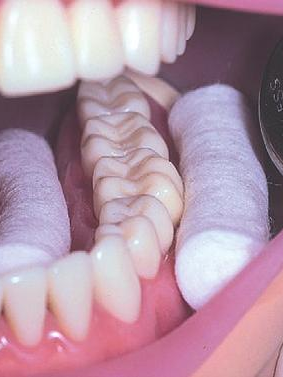

以常见的“树脂基质窝沟封闭剂”为例,其流程大致包括:清洁牙面、隔湿、酸蚀、冲洗干燥、涂布粘结剂、光固化、检查。1次隔湿(如下图),通常可做1-2颗牙,或邻近的多颗牙,操作下来需要5-10分钟。窝沟封闭的时间,主要取决于需要隔湿几次。